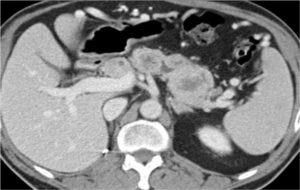

Хирургическое вмешательство – один из способов лечения солидного рака

Реальная тактика, как правило, содержит комбинацию двух или более методов. Ее формируют так, чтобы максимизировать воздействие на опухоль и снизить негативную нагрузку на организм больного.